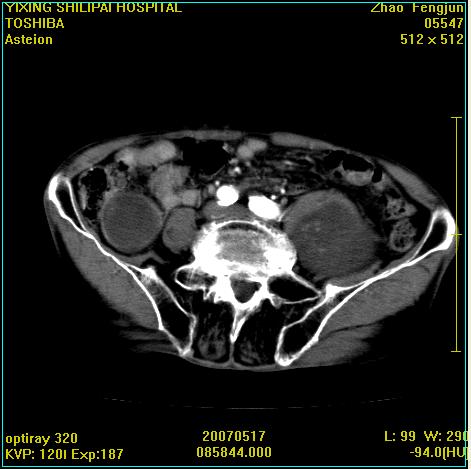

考虑:1、左侧腰大肌囊实性占位性病变(囊性神经根鞘瘤?);

2、右侧兰尾区囊性占位性病变(兰尾囊肿?囊腺癌?类癌?)

以下是引用xiaoniu在2007-5-26 10:45:00的发言:[br]腰大肌的病变应该没有问题,增强扫描还有轻度强化及细小血管影入内,应该排除脓肿,考虑占位性病变,腰大肌的占位多考虑:神经源性肿瘤。另外腹主动脉下端有真假腔的强化,考虑:主动脉夹层。[br][br][本贴已被 xiaoniu 于 2007-5-26 10:46:39 修改过]

以下是引用老爱克斯新网客在2007-5-26 18:26:00的发言:[br]1左下腹囊实性占位肿块,增强后不均匀强化,位于脊柱旁,椎体骨质无破坏软组织无肿胀,考虑神经源肿瘤神经鞘瘤可能大,2右下腹囊性占位性病变,增强后囊壁强化,考虑阑尾囊肿或囊腺瘤,